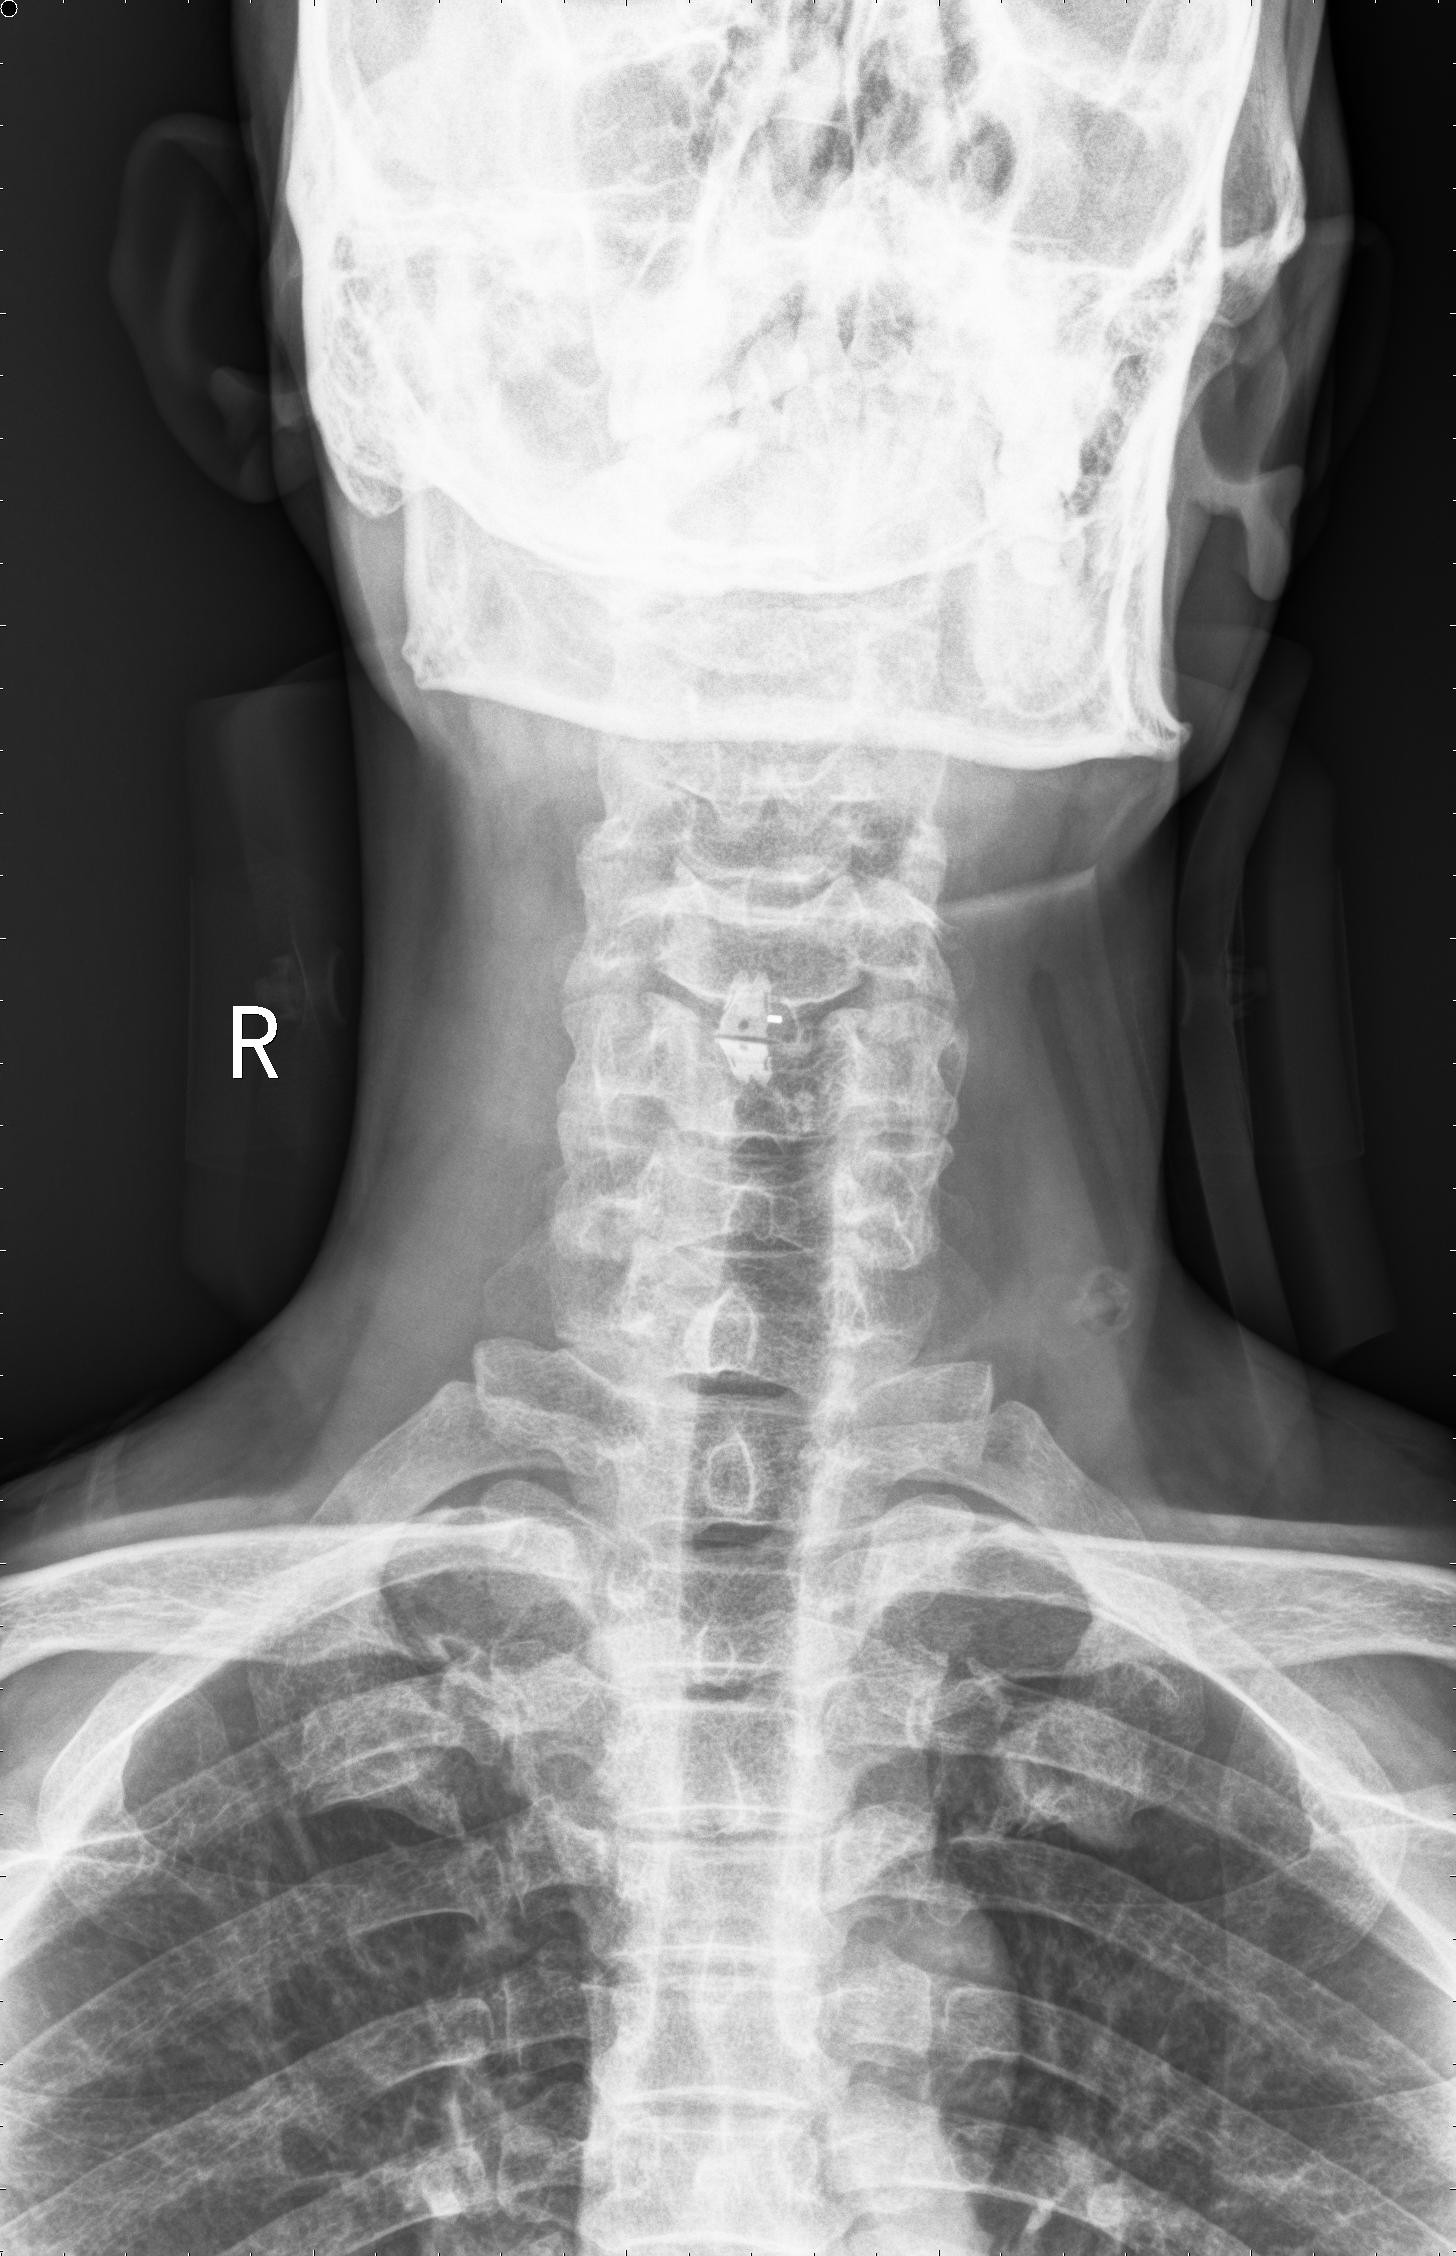

中年男性41岁,因“行走不便2年,加重伴双手麻木2周”之主诉入院,症状主要为:颈部疼痛、僵硬,双下肢无力、行走不稳,双手麻木,协调性差,右手握笔困难。入院查体:步态不稳,C3-C7压痛、叩击痛,肢痛温觉减退,双上肢肢肌力5-级,双下肢肌力4-级,肌张力增高,双下肢腱反射亢进,病理征(+),行颈前路小切口突出椎间盘切除、前路颈椎桥形锁定植骨融合(ROI-C假体),无需前路钢板,术后四肢麻木明显缓解,右上肢精细动作明确增强,可写字,行走不稳消失,肌力基本正常,颈部活动度无明显受限。(图1、图2)

图2:术后颈椎X线提示颈椎桥形锁定融合居中,椎间隙高度恢复正常,融合良好。